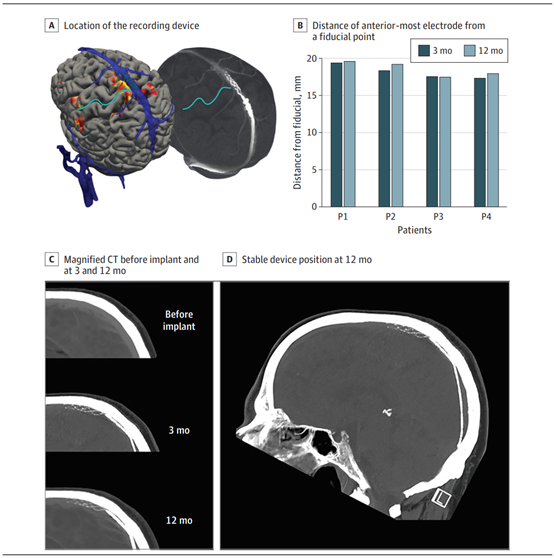

植入前经磁共振成像(MRI)研究评估神经解剖学和静脉通路植入的适用性。在尝试下肢运动时,通过血氧水平依赖的功能性MRI评估保留的运动皮层激活。通过三维数字减影血管造影引导设备交付,并将其与术前结构MRI标记的目标位置同步。BCI使用2 mm导尿管经颈静脉到达上矢状窦(SSS)的目标位置,并部署在靠近中央前回的位置(图2A)。

图2. 12个月的血管内电极阵列放置和迁移。A.记录装置位于毗邻运动皮层的上矢状窦。中央前回位于中央沟的正前方(青色线)。左图显示了植入前磁共振成像的三维渲染图,在尝试移动过程中有明显的激活区域,并突出显示了植入电极(绿点)。右图为植入后3个月的三维计算机断层扫描(CT)。B-D.植入后3个月和12个月,装置位置稳定。B.条形表示植入后3个月(深蓝色)和12个月(浅蓝色)CT测量的最前端电极到基准点的距离,描绘了所有患者时间点之间的亚毫米差异(0.45±0.28mm)。C.植入前、植入后3个月和12个月的放大CT。D.植入后12个月的全头部CT。

在主要终止节点评估中,在植入术和12个月随访期间,没有发生导致死亡或永久性残疾的器械相关严重不良事件。研究期间未发生严重的器械不良反应或不相关的严重不良事件。有8例不良器械反应,这些不良反应被归类为轻度,无需干预即可解决(表2;不严重的事件包括头痛和切口部位的瘀伤。对于次要终止节点,回顾3个月和12个月的CT静脉造影,4例患者均未发现目标血管闭塞或血栓形成。在3个月和12个月的静脉造影中,远端电极与基准线之间距离的值为0.45±0.28mm,表明装置位置在临床上没有显著变化(图2)。